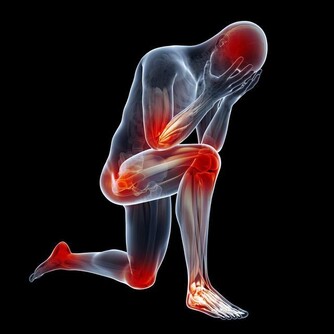

骨質疏鬆症的主要特徵是骨礦物質含量低下、骨強度降低、易發生骨折等。上了年紀的老人家走路駝背、身高降低,其實都是骨質疏鬆症的表現。

與此同時,骨質疏鬆症也被稱為“沉默的殺手”。因骨頭“變脆”,容易導致骨折。

在年齡大於50歲的中老年人群中,女性得骨質疏鬆的機率比男性大得多,且在今後的生活中會發生骨質疏鬆相關的脆性骨折。而骨折後,臥床期間死亡率極高,骨質疏鬆也因此被稱為“老年人最後的喪鐘”。